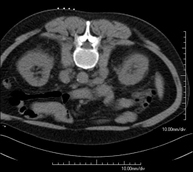

- Abdominal and pelvic CT

Diagnostic test that consists of obtaining high-definition anatomical images (bone structures, vascular structures, liver, pancreas, gallbladder, kidneys, adrenal glands, spleen, small and large intestine, bladder, uterus and ovaries, prostate and seminal vesicles, ureters, etc.) using CT (computed tomography) equipment. Most studies require the use of iodinated contrast.

- Kidney CT

Diagnostic test that involves obtaining high-definition anatomical two- and three-dimensional images of the kidney and urinary system using CT (computed tomography) equipment. The study is performed before and after the use of iodinated contrast in different ‘renal phases’ for functional and anatomical assessment (renal parenchyma, ureters, urinary bladder, renal arteries and veins, etc.), as well as adjacent structures (inferior vena cava, abdominal aorta, liver, spleen, etc.). It is particularly recommended when kidney damage is suspected, in patients with blood in their urine or haematuria, etc.